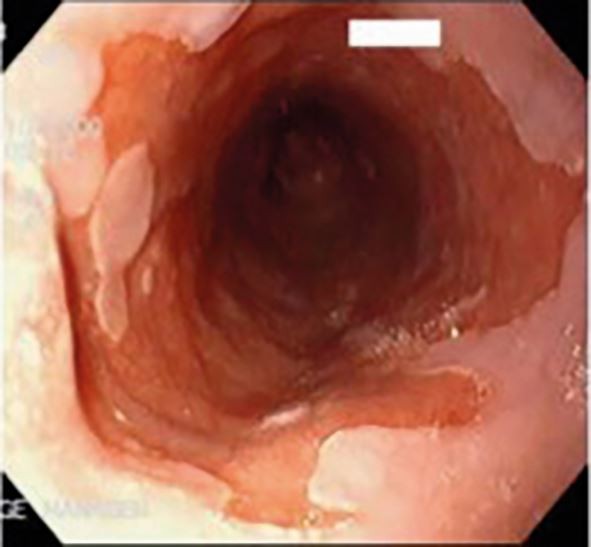

Diagnosis is often clinical; however, upper endoscopy is warranted for red flag symptoms, or no improvement after eight weeks of medical treatment. The role of endoscopy is to confirm diagnosis (erosion/ulcerations or non-erosive reflux disease), exclude atypical causes (eosinophilic esophagitis, candida, herpes simplex) and diagnose complications (Barrett's oesophagus, stricture, adenocarcinoma) (Fig. 6, Fig. 7, Fig. 8).